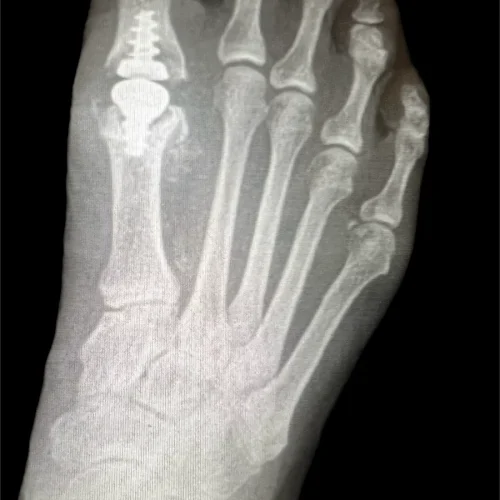

Surgical Intervention at Stepwell Institute is never a “one-size-fits-all” solution. We view surgery as a precise tool used to restore the natural biomechanics of the foot and ankle when non-invasive methods have reached their limit. Our philosophy centers on individualized surgical planning—using advanced imaging to map out the procedure before you ever enter the operating room. From correcting bunions and hammertoes to performing ligament repairs and fracture fixations, Dr. Yakov utilizes techniques designed to minimize trauma to the surrounding tissues, thereby reducing the risk of complications and ensuring a more stable, long-term result for our patients.

Our Case Study